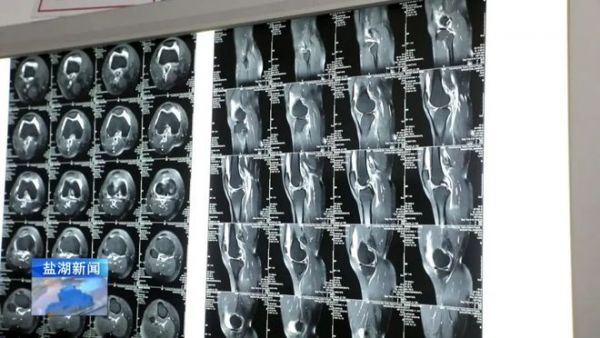

這個(gè)病人來了之后,通過我們專業(yè)的查體,再加上核磁輔助診斷,最終我們判斷她是運(yùn)動(dòng)過度引起的膝關(guān)節(jié)損傷。

這種損傷就是髂脛束摩擦綜合征的表現(xiàn),俗稱跑步膝。